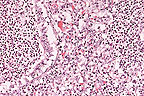

Cellular atypia in the basal layer of the epithelium in a squamous cell carinoma in situ in a hairless mouse. (HE, 400X, 106K)

The skin sections show the typical lesions induced by ultraviolet radiation. Epidermal changes include intracellular edema, particularly prominent in the stratum basale, hyperkeratosis (occasionally parakeratotic), hyperplasia with prominent atypia of epidermal cells and occasionally hyaline degeneration of keratinocytes with pyknotic nuclei. In some areas, clefts are formed at the dermo-epidermal junction. Occasionally, intraepidermal pustules are present, and in localized areas the entire epidermis is necrotic. In the dermis moderate mixed inflammatory cell infiltration is present which also extends to the adjacent subcutis. The skin of untreated mice exposed to the same light intensity showed no abnormalities. Therefore it can be concluded that the observed skin lesions represent a phototoxic reaction.

AFIP Diagnosis: 1. Haired skin: Squamous cell carcinoma in situ, mouse (albino hairless Ibm: MORO-hr strain), rodent. 2. Haired skin: Folliculitis and furunculosis, pyogranulomatous, diffuse, mild to moderate, with intraepithelial pustules, erosions, and ulcers.

Conference Note: The diagnosis of squamous cell carcinoma in situ is based on the significant degree of atypia of the epidermal and follicular epithelial cells, the presence of increased numbers of mitotic figures some of which are bizarre, anisokaryosis, anisocytosis, and multiple, irregularly shaped nucleoli. Neoplastic epidermal/follicular epithelial cells do not breech the basement membrane zone.